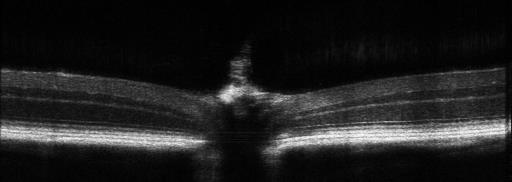

與常規(guī)50°視野角度相比,90°大視野系統(tǒng)單次掃描可以同時(shí)獲取視乳頭和視網(wǎng)膜后極部的斷層結(jié)構(gòu)信息,減少不必要的多次多位置采集,同時(shí)更容易找到病變位置,極大的減少實(shí)驗(yàn)者的工作量。